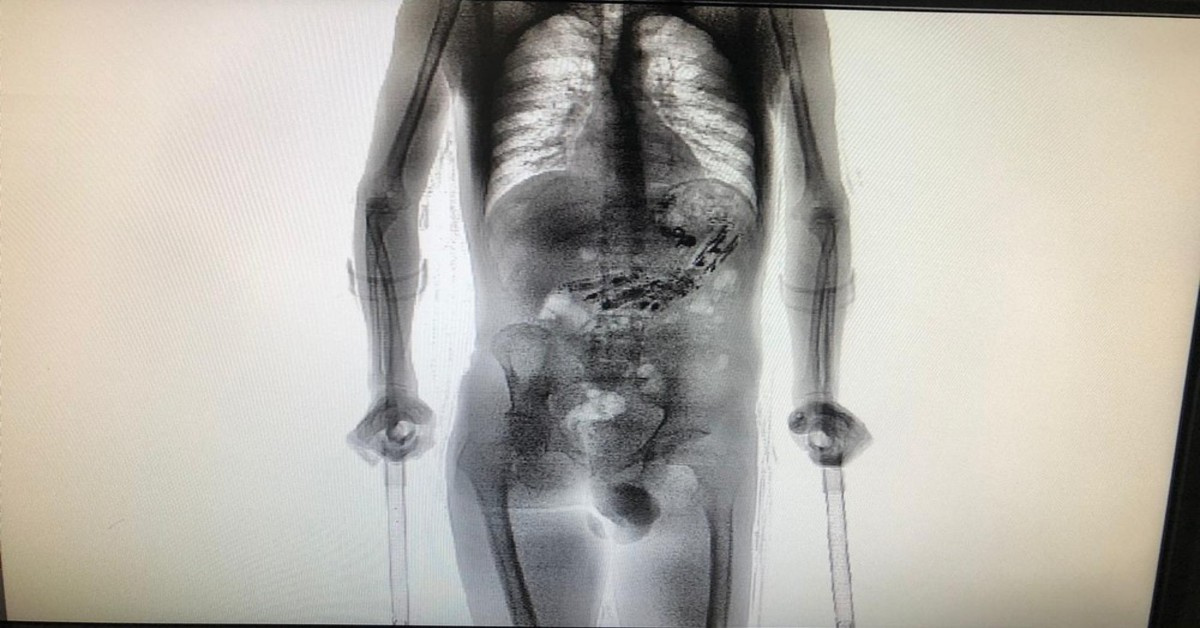

O jovem de 24 anos cumpre pena na Colônia Agrícola Penal de Palhoça, na Grande Florianópolis, e foi flagrado ao passar por um scanner durante a revista, ele teve que ser levado a um hospital para fazer uma cirurgia para retirada dos objetos de seu estômago, que somaram 61 objetos.

O jovem teria ficado sete dias fora depois que recebeu o benefício da saída temporária, ao passar pelo scanner, o aparelho detectou os objetos: 9 celulares e outros 52 objetos, todos no estômago do jovem, e uma quantidade de drogas.

Depois que o detector de metal sinalizou algo errado com o detento, os agentes tiveram que levá-lo ao Complexo Penitenciário do Estado, em São Pedro de Alcântara, onde ele passou pelo scanner que dá uma visão do que há no interior.